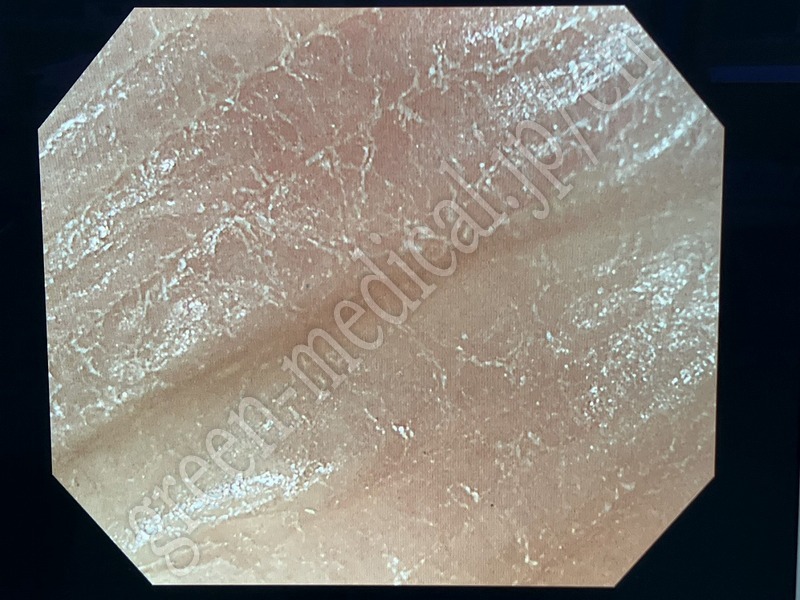

Video Colonoscope .PCF-H290ZI

OLYMPUS

.PCF-H290ZI

115905